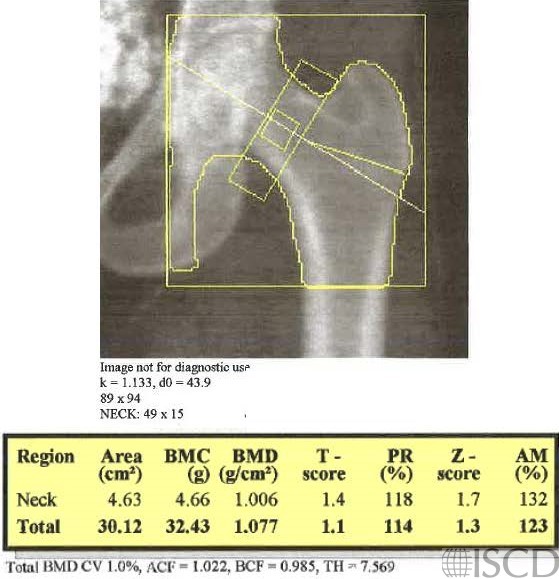

A calcified uterine fibroid is seen within the pelvic brim. The pelvic ultrasound showed a 6.2 x 4.1 x 6.4 cm uterine fibroid int he left mid uterine body. The fibroid is not within the region of interest scan in the left proximal DXA scan.

The DXA scans show examples of uterine fibroids seen as internal artifacts.

Sarah L Morgan, MD, RD, CCD, The University of Alabama at Birmingham (bottom image)